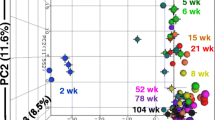

To investigate sex-dependent expression of miRNAs in the hippocampi of rats in response to alcohol, we performed miRNA expression profiling using microarrays. After log2 transformation of the magnitude of miRNA up- or downregulation (fold change cutoff of 1.5 as compared to the control groups), a hierarchical heatmap of 153 miRNAs was constructed (Fig. 3a). Of 153 differentially expressed miRNAs, 89 were differentially expressed in male rats only, while 35 were differentially expressed in female rats only (Fig. 3b and Supplementary Table 1). In addition, 29 miRNAs were upregulated or downregulated by alcohol in both sexes. Of 118 miRNAs differentially expressed in male rats, 6 miRNAs including miR-125a-3p were significantly upregulated in the MA group, while 3 miRNAs including miR-324-5p were significantly downregulated in the MA group (Fig. 3c). In female rats, of 64 differentially expressed miRNAs, 4 miRNAs including miR-881-3p were significantly downregulated in the FA group, while 3 miRNAs including miR-500-3p were significantly upregulated in the FA group (Fig. 3d).

miRNAs expressed differentially between control and alcohol-treated groups. a Heatmap described from the two-way hierarchical clustering analyses of differentially expressed (more than 1.5 fold) miRNAs among groups. The hippocampi of four rats in each group were used for the miRNA array. b Venn diagram showing the number of differentially expressed miRNAs between two groups. MA, male alcohol-treated group; MC, male control group; FA, female alcohol-treated group; FC, female control group. c Comparison of miRNA expression in the male control and alcohol-treated rats. d Comparison of miRNA expression in the female control and alcohol-treated rats. e Validation of 3 miRNAs upregulated in alcohol-treated male rats (n = 4) compared to the control male rats (n = 4) using RT-qPCR. f Validation of 2 miRNAs downregulated in alcohol-treated female rats (n = 4) compared to the control female rats (n = 4) using RT-qPCR. *Significantly different from control group in each sex (*p < 0.05)